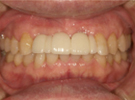

30代女性

事故のため、前歯を2本失いました。

インプラントと矯正治療をしました。

| 治療前 | ||

| インプラント後、仮歯を入れました。 | ||

| 矯正設置を着用し、歯列矯正を行いました。 | ||

| 治療後 | ||